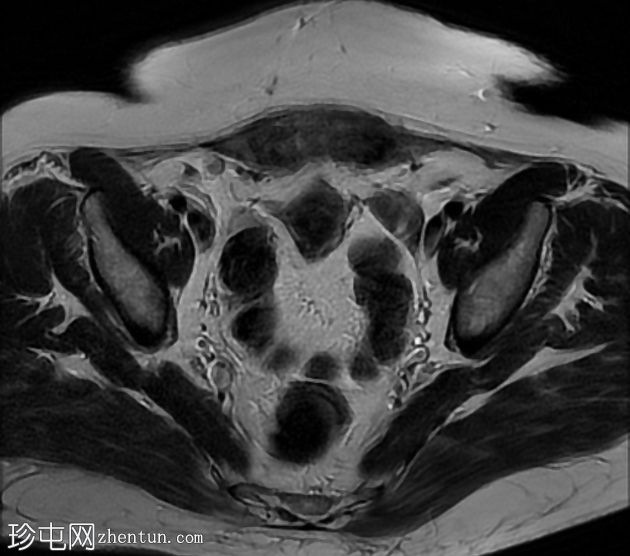

轴向

T2

腹直肌双侧不规则病变。它们在 T1WI 上引起等信号至高信号,T1 脂肪饱和度上出现高强度出血灶,T2 WI 上出现低信号,造影后增强,代表腹壁子宫内膜异位症。

腹壁子宫内膜异位症延伸至子宫前浆膜深处,下方为前体局部浆膜下低信号病变,代表相邻的子宫腺肌瘤。子宫也显示剖宫产微环境。

正常附件和卵巢。

该病例显示腹壁前子宫内膜异位症延伸至子宫深处,显示相关的前子宫腺肌瘤。

剖宫产疤痕子宫内膜异位症可位于皮肤、皮下组织、直肌/鞘、腹膜内或子宫肌层(子宫疤痕内)。